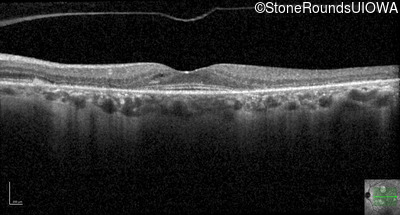

Optical Coherence Tomography - Left - 20/20 -2

Exemplar / OCT Stack

OCT Stack